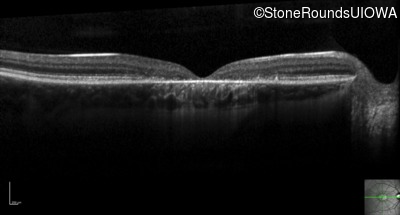

Optical Coherence Tomography - Left - 20/100 +1

Exemplar / OCT Stack